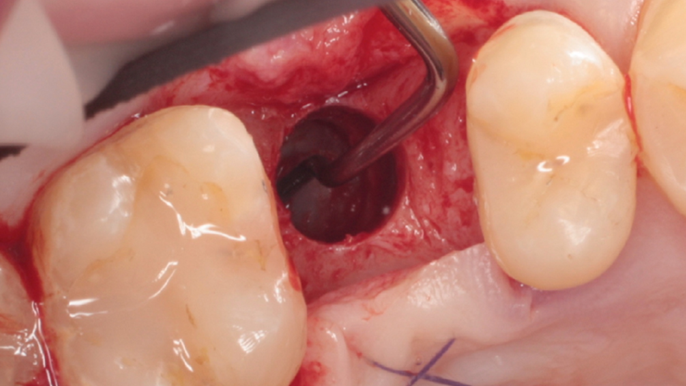

Clinical case: # 46 implant placement & GBR using i-Gen membrane for significant vertical resorption & mixed bone defect

- Courtesy of Dr. Iulian Filipov, Romania -

AnyRidge, mandibular posterior, i-Gen, resorption, bone defect, bone regeneration, space management, #46, GBR, Dr. Iulian Filipov

AnyRidge implant system, i-Gen